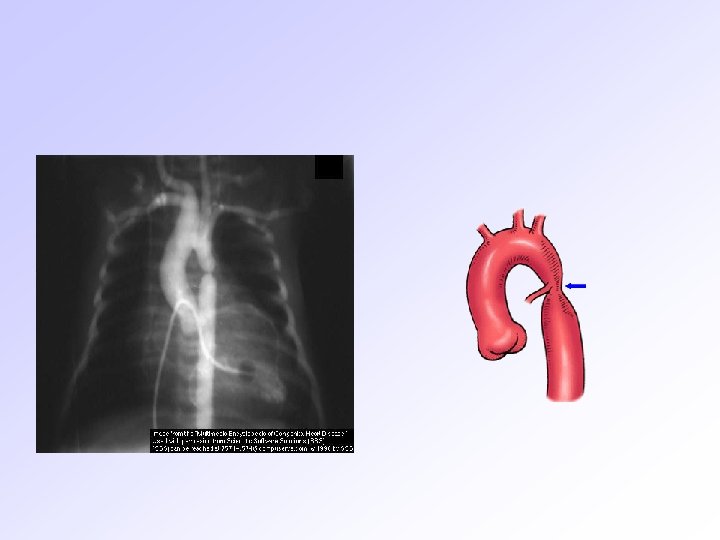

Laboratuvar bulguları TELE Kalp büyüklüğü normal veya küçüktür. RV hipertrofisi nedeniyle apeksin yukarı kalktığı ve ana PA’nin konkav olduğu görülür. (couer en sabot) RA genişleme (%25) ve sağ aortik ark(%25) görülebilir